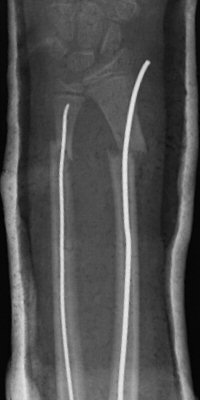

Distala diafysära radius- och ulnafrakturer, opererade med TEN-spikar, sista bilderna läkt efter 7 månader. Alla bilderna är från samma patient.